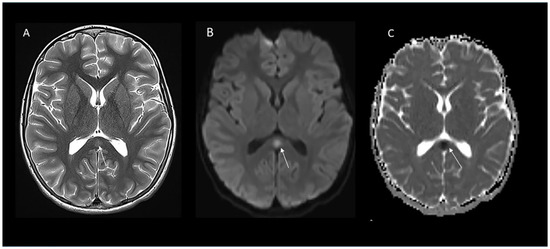

Background/Objectives: Mild Encephalopathy with Reversible Splenial Lesion (MERS) is a potential complication of certain viral infections, but adult cases involving influenza are rare in the literature. Here, we report a case of a 31-year-old Chinese gentleman with an atypical presentation of Influenza B-associated mild encephalopathy with reversible splenial lesion (MERS). Methods: This is a case report with a detailed chronology followed by a discussion of pathophysiology. Results: The patient presented acutely to the tertiary hospital with a severe headache and a peculiar automatism pattern of behaviour involving intermittent screaming, involuntary jerking movements of the upper limbs, and incoherent speech, which culminated in an episode of tonic–clonic seizure lasting 3 min. Symptoms started on the day that the patient was diagnosed with Influenza B and given the antiviral Baloxavir by his GP. Clinically, there was high anion gap metabolic acidosis with hyperlactatemia, rhabdomyolysis, hepatitis transaminitis and absolute lymphopenia. Nasopharyngeal swab PCR and immunofluorescence was positive for Influenza B. EEG was normal, but an MRI of the brain showed a cytotoxic lesion of the splenium of the corpus callosum. The patient was started on Oseltamivir and made a complete neurological recovery, with a repeat MRI showing resolution of the splenial lesion at 3 months. MERS is a rare clinic-radiological syndrome characterized by a transient encephalopathy and a reversible lesion in the splenium of the corpus callosum, which has been reported mostly in the pediatric population. Conclusions: This case report of an influenza B-triggered MERS in an adult highlights the importance of maintaining MERS as a differential for acute encephalopathy in adults with a viral prodrome. Full article

Clinically mild encephalitis/encephalopathy with reversible splenial lesions (MERS) is a mild form of encephalitis/encephalopathy that appears in association with various conditions, including infection. COVID-19 is also known to cause MERS. MERS more commonly occurs in children, and adult cases are relatively rare. Typical head MRI findings include a round lesion in the mid-layer of the corpus callosum with a high signal intensity on diffusion-weighted images. Most improve within a week. Although the exact mechanism by which the cerebral corpus callosum is affected is still unknown, several hypotheses have been proposed, including the involvement of electrolyte abnormalities (e.g., hyponatremia) and inflammatory cytokines (e.g., IL-6). In this report, we describe the first case of COVID-associated MERS with a typical imaging course and hyponatremia, with a review of the relevant literature. When psychiatric symptoms and the disturbance of consciousness appear in COVID patients, MERS should be considered in addition to delirium due to fever and hypoxia. Full article

A 12-year-old male was presented to the hospital with acute encephalopathy, headache, vomiting, diarrhea, and elevated troponin after recent COVID-19 vaccination. Two days prior to admission and before symptom onset, he received the second dose of the Pfizer-BioNTech COVID-19 vaccine. Symptoms developed within 24 h with worsening neurologic symptoms, necessitating admission to the pediatric intensive care unit. Brain magnetic resonance imaging within 16 h of admission revealed a cytotoxic splenial lesion of the corpus callosum (CLOCC). Nineteen days prior to admission, he developed erythema migrans, and completed an amoxicillin treatment course for clinical Lyme disease. However, Lyme antibody titers were negative on admission and nine days later, making active Lyme disease an unlikely explanation for his presentation to hospital. An extensive workup for other etiologies on cerebrospinal fluid and blood samples was negative, including infectious and autoimmune causes and known immune deficiencies. Three weeks after hospital discharge, all of his symptoms had dissipated, and he had a normal neurologic exam. Our report highlights a potential role of mRNA vaccine-induced immunity leading to MIS-C-like symptoms with cardiac involvement and a CLOCC in a recently vaccinated child and the complexity of establishing a causal association with vaccination. The child recovered without receipt of immune modulatory treatment. Full article